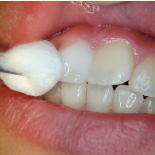

下の写真の一番左は実は治療前の写真です。痛みもなく一見問題なく入っている銀歯も除去してみると中に虫歯が。殺菌作用のある薬を詰めて治療中です。外からは分かりずらい虫歯も多いので定期検診がおすすめです。

- 治療前

- 除去

- 治療中